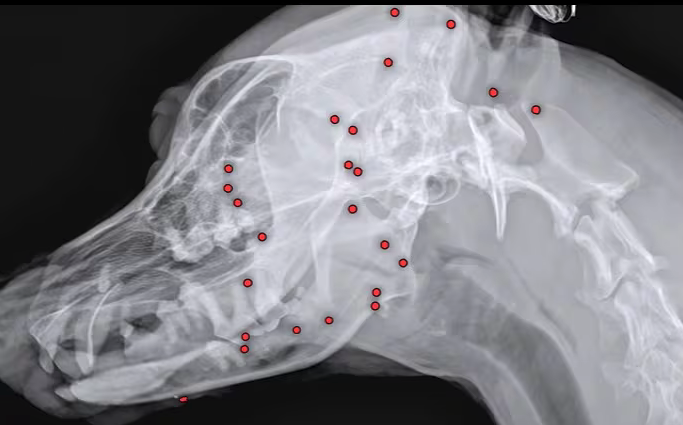

온몸에 총알 파편 수십 개가 박힌 채 돌아다니던 백구가 발견돼 구조된 가운데, 새 가족을 찾고 있다. 25일 VIP동물의료센터는 최근 구조한 유기견 백구의 몸에서 70개가 넘는 산탄총 파편이 박혀 있는 것을 발견해 제거에 나섰다고 밝혔다. 구조 당시 백구의 겉모습에서는 총알 자국을 확인할 수 없었다.

의료센터 측은 백구의 해외 입양을 앞두고 건강 검진을 위해 X레이 촬영을 했다가 산탄총 파편을 발견했다. 이로 인해 백구의 입양도 불가능해졌다. 의료센터 측은 곧바로 엑스레이, CT(컴퓨터 단층촬영) 등 정밀 검사에 들어갔다. 안승엽 VIP동물의료센터 원장은 "총알이 머리 쪽부터 어깨, 가슴통, 엉덩이, 다리까지 너무 많이 있었다"며 "살아있는 게 기적"이라고 말했다.

산탄총 파편 제거 수술은 3시간 넘게 진행됐다. 맨눈으로 탄알을 다 확인할 수 없어서 투시기를 이용해 수술 시간이 길어졌다. 안 원장은 "탄알을 한 번에 다 제거하기는 현실적으로 어려워 백구의 얼굴을 위주로 최대한 많이 제거하는 방향을 선택했다"며 총 26개의 파편을 제거했다고 설명했다. 병원 측은 추후 제거한 파편의 성분 분석 등을 통해 추가 수술 여부를 검토할 계획이다.